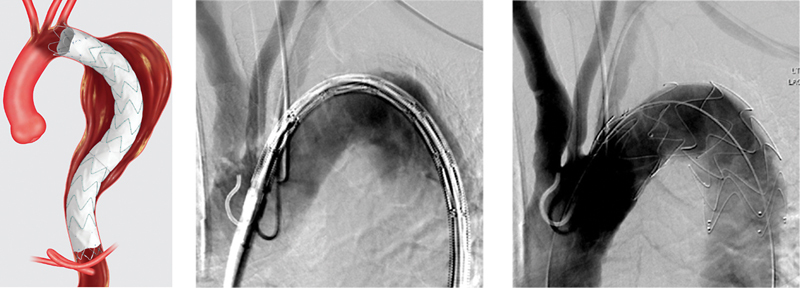

Aortic aneurysms represent the 15th leading cause of death in men and women over 55 years of age. Where historically these lesions were all addressed via an open approach, endovascular aortic repair has entirely altered the way that surgeons approach aortic lesions. Although it was initially employed for patients who were poor surgical candidates, endovascular repair is now standard for abdominal aortic aneurysms and aneurysms in the descending thoracic aorta. Open surgery remains the gold standard for management of ascending aneurysms, in part due to the limitations portended by the anatomy of the ascending aorta, although increasing evidence suggests that endovascular approaches are feasible and may sometimes be optimal for patient outcomes. Here, we present some of the anatomical and technical challenges of the endovascular approach to these "Zone 0" aneurysms, the associated complications, and the current state of device development.